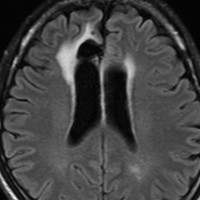

局所照射後の白質変性,脳質壁の白質変性

全脳照射でなくても局所照射でも放射線治療後には白質変性が生じます。無症状のことが多いですが,照射野内の脳萎縮などを伴うと高次脳機能障害などの症状をだすことはあります。

この患者さんは右前頭葉のびまん性星細胞腫に46グレイ23分割という低い線量の局所照射をしました。放射線治療8年後のMRI FLAIR画像です。腫瘍の再燃はなく,脳室周囲の白質が高信号になっています。脳梁や透明中隔の白質組織も高信号になり,非常に軽度の白質変性を示しています。でも,何の症状もありません。注意しなければならないのは,この所見を星細胞腫の再発あるいは進行と捉えて余分な治療をしないようにすることです。とくにグレード2の星細胞腫と乏突起膠腫の時に問題となります。